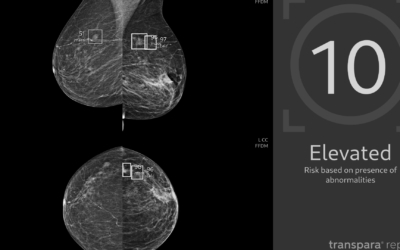

Najde o půlku víc nádorů. Umělá inteligence jako pomoc lékařům v mamografii se má v Česku rozšiřovat

Pilotní projekt umělé inteligence, která pomáhá lékařům hledat nádory prsu, podle dosavadních čísel ukázal svůj přínos. EUC ho hodlá rozšiřovat.